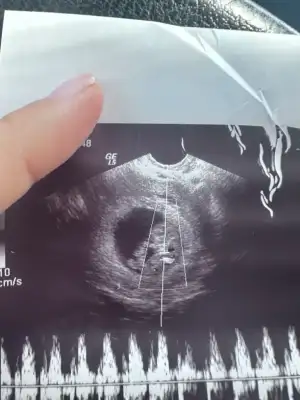

Kızlar benim bebişim de 9+0 da 😍 kese önceli haftalarsa yusyuvarlaktı şimdi şekli değişmiş. Doktor kız gibi tahmin ediyorum dedi. Sizde hislerinizi söyler misiniz 😍

• IMG_8815.webp

IMG_8815.webp

27,5 KB · Görüntüleme: 66